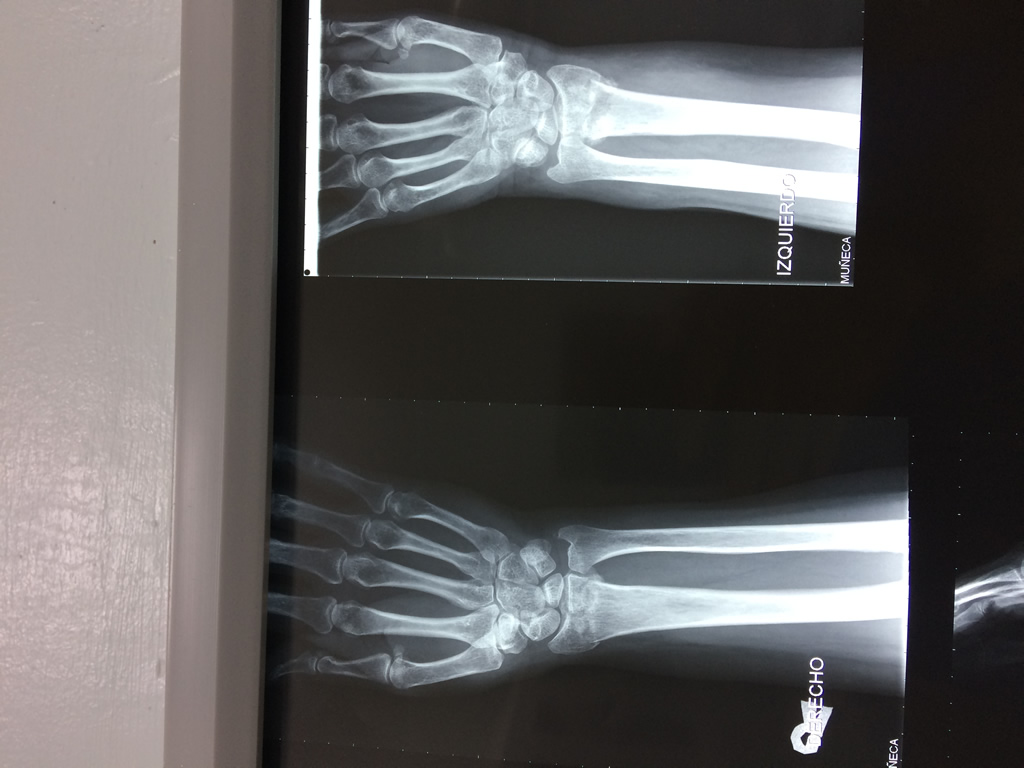

Cirugías de Codos - Cirugías de Muñecas y Manos

Los procedimientos más comunes en cirugía de la mano son aquellos destinados a reparar traumatismos, incluyendo lesiones de tendones, nervios, vasos sanguíneos, y articulaciones; huesos fracturados; y quemaduras, cortes, y otros daños de la piel.